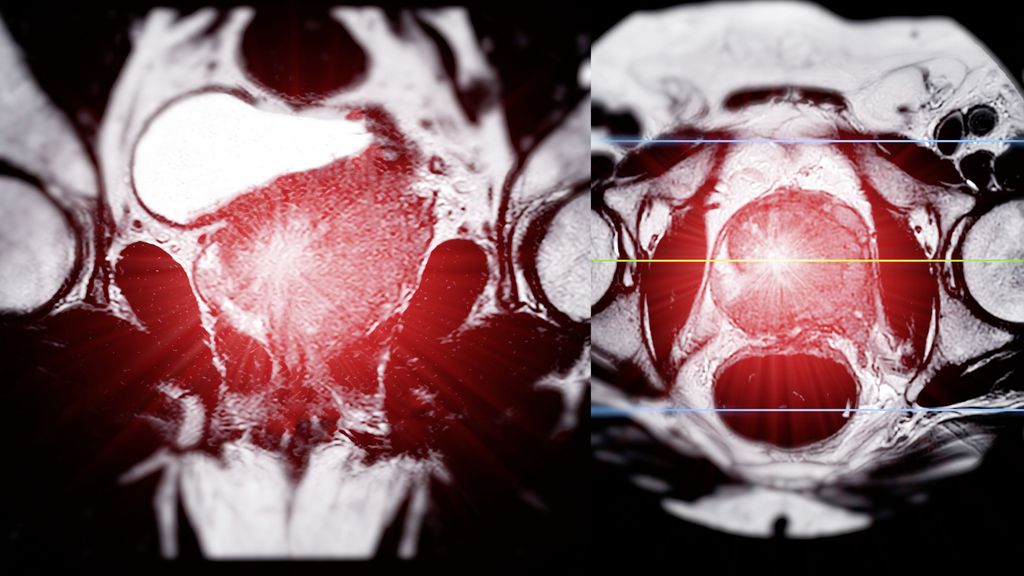

Le paysage thérapeutique du cancer de la prostate avancé a évolué et s’est enrichi presque chaque année depuis 2014 et la première présentation de l’étude CHAARTED. Aujourd’hui, les ...